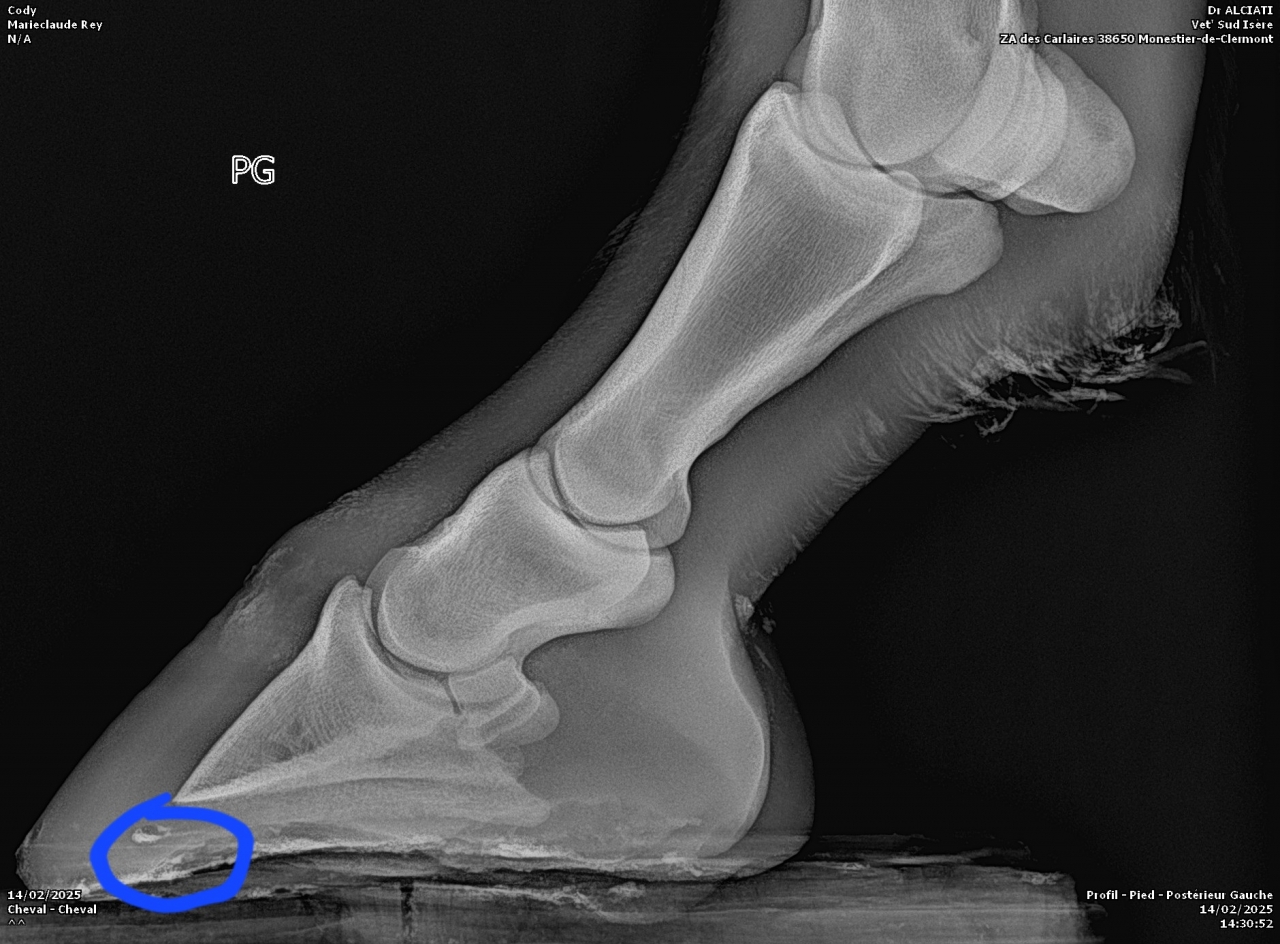

| Dire merci | Voici les radios :![]() ![]() |

DéconnectéDire merci | Personne n'a répondu à tes photos de radios parce que je suppose que comme moi, on ne se sent pas compétent pour l'interpréter. Qu'en dit le véto ? Il a bien dû te donner un diagnostic? Moi je ne vois pas de keratome mais un truc louche sur le processus palmaire du côté droit de la photo. Et l'ensemble qui part quand même bien de travers en vue de face, mais je ne sais pas si c'est dû à la position du pied sur la cale ou si c'est l'angle naturel. Pas l'impression que la sole soit si fine que ça, si? |

| Dire merci | Merci pour la réponse ![]() De ce que j'ai compris, l'anomalie serait la poche de sang (entouré en bleu) : ![]() ![]() C'est de travers car les radios ont été faites sur un terrain en pente. |